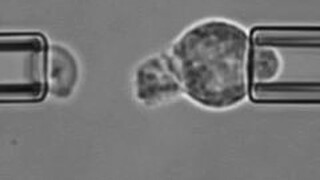

นักวิทยาศาสตร์ "ล้อเล่น" เซลล์นิวโทรฟิลภายใต้กล้องจุลทรรศน์